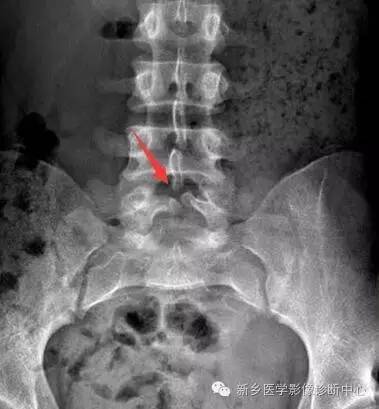

X线:棘突、椎板缺损

(1)隐性脊柱裂:神经管几周围组织已闭合,椎弓存在裂隙,由纤维组织、软骨组织连接,无脊膜或神经组织膨出。

多发生于腰骶部,偶见于颈胸段。